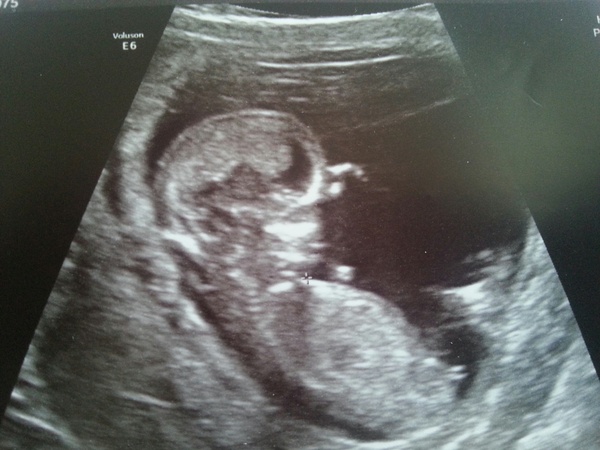

Just wanted to share my wee pic....can't stop looking :)

12+3